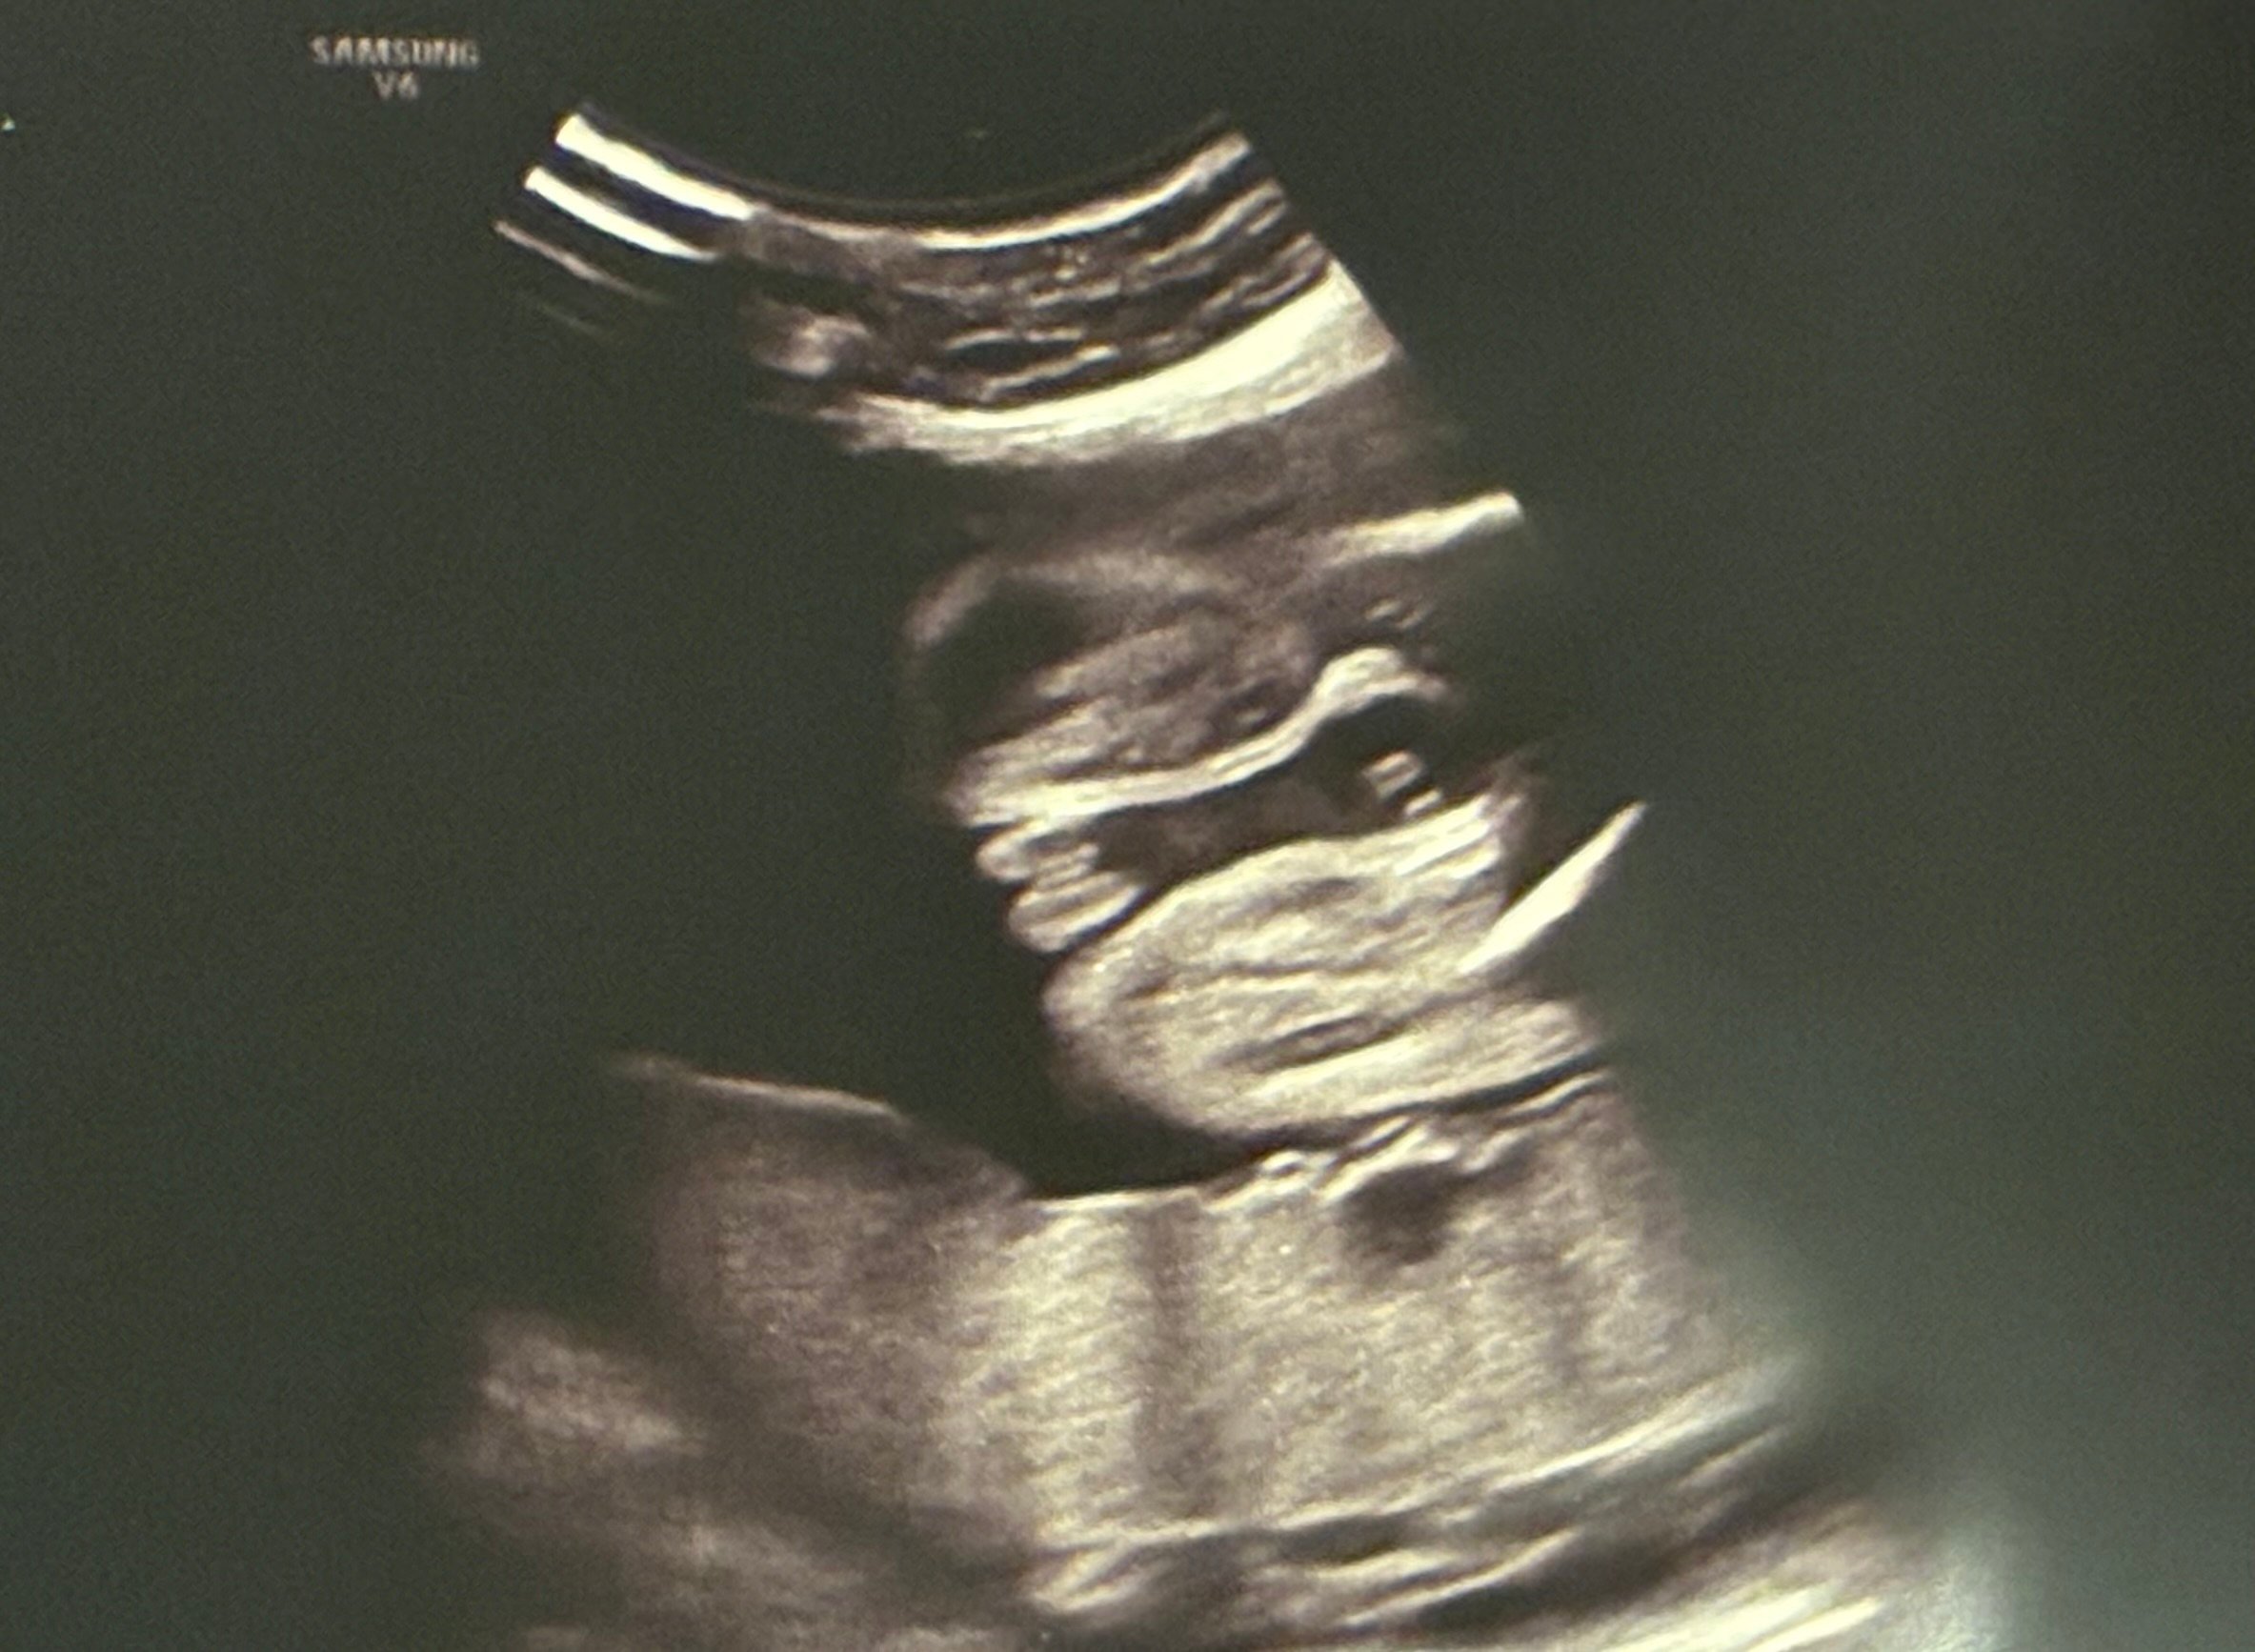

ما هو نوع جنس الجنين كما هو موضع في صورة السونار في الاسبوع ١٧ شاكرة لكم

ما هو نوع جنس الجنين عمر الحمل ١٦ اسبوع و يوم ؟